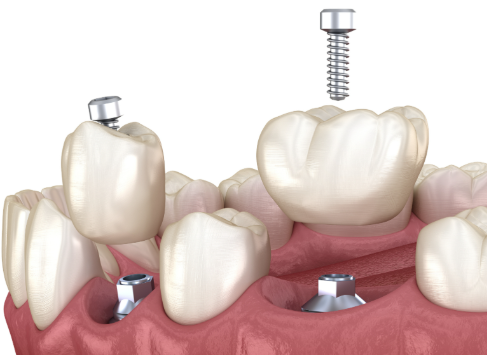

活动义齿一般多少钱一颗费用?2026年最新价格揭秘! 文章揭秘2026年活动义齿最新价格。通常镶活动假牙一颗1000 - 3000元,不同类型费用有别。如隐形义齿1000 - 1200元,便宜但寿命短、咀嚼差;钴铬合金等1500 - 2000元,强度好、使用久;纯钛基托2000 - 3000元,舒适美观。此外,地区、医院等级和医生水平也影响价格,选义齿要综合考量。 活动义齿 2026年03月04日 0 点赞 0 评论 7 浏览

活动义齿哪种最舒服还不伤害基牙?揭秘3种最佳选择! 本文围绕“活动义齿哪种最舒服还不伤害基牙”展开。首先强调了活动义齿舒适与护基牙的重要性,接着介绍了纯钛金属基托活动义齿等三种义齿的特点,包括舒适度、对基牙的影响、价格等。还给出选择建议,要考虑口腔状况、经济因素,并听取医生建议。最后提醒佩戴后注意适应期、清洁和饮食,综合考量选适合自己的义齿。 活动义齿 2026年03月04日 0 点赞 0 评论 12 浏览

补一颗活动义齿多少钱?揭秘真实费用与选择技巧! 本文围绕补一颗活动义齿的费用及选择技巧展开。费用大致在100 - 300元,受材料、修复难易、医院级别、当地经济等因素影响。不同材料义齿各有特点和价格区间。选择时要综合自身情况,选正规机构,多对比。此外,后期维护有成本,需正确佩戴清洁。提醒大家综合考量价格、质量和舒适度,必要时咨询医生。 活动义齿 2026年03月04日 0 点赞 0 评论 7 浏览